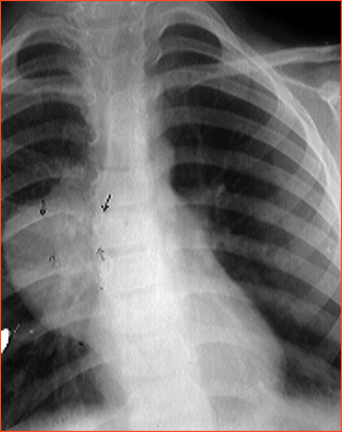

Rx toracică, incidență P-A

DESCRIERE:

pe tot teritoriul pulmonar, bilateral → opacități nodulare multiple de dimensiuni variabile, intensitate medie-mare, omogene, cu contur net

distribuție anarhică

blocuri adenopatice la niv. hilurilor pulmonare

DX: MTS pulmonare hematogene

DD:

hidatidoză - dimensiuni mai mari

bronhopneumonie - contur neregulat, neomogene, distribuție bazală